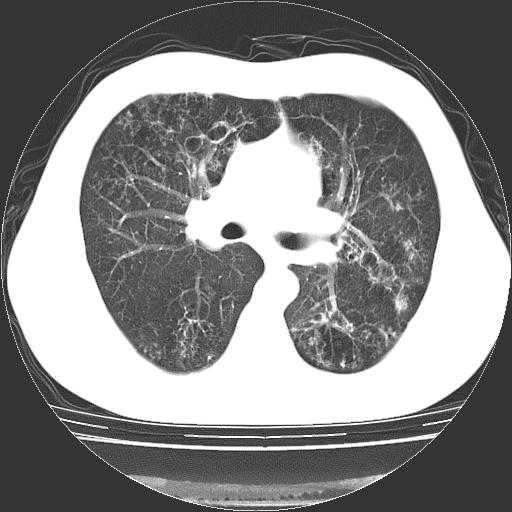

以下是引用zyx168在2006-12-4 15:30:00的发言:[br]经典!支气管肺囊肿并感染。

以下是引用dyqct在2006-12-4 17:11:00的发言:[br]典型的囊状支扩合并感染。

以下是引用liaoqiang在2006-12-4 16:12:00的发言:[br]局部肺叶内可见扩张的支气管壁,考虑为支扩。部份囊样影内有小液平和肺内散布斑片征影、小结节及纤维灶,提示支扩伴感染,且由于局部呈现有树芽征感染以结核可能性大。

以下是引用zhoucan076在2006-12-4 16:48:00的发言:[br]囊状支扩合并感染